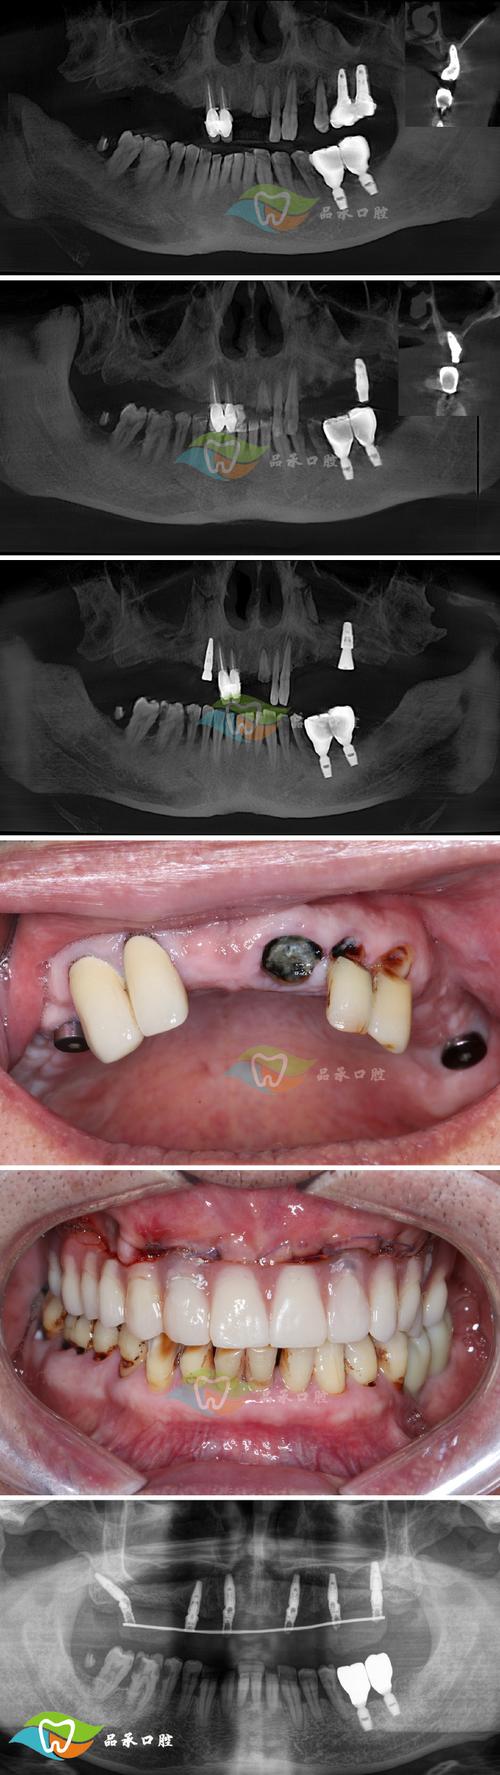

骨粉植入后,其吸收与骨再生是一个动态平衡的过程,术后1-2周为炎症期,植入区血运重建,炎性细胞浸润骨粉颗粒表面,启动“清道夫”作用;术后1-3个月为骨结合期,破骨细胞开始缓慢吸收骨粉,同时成骨细胞在骨粉周围沉积新骨,形成“骨-骨粉”复合结构;术后3-6个月进入改建期,新骨逐渐替代骨粉,骨结构趋于成熟,最终骨粉完全被自体骨替代,形成具有生理功能的骨组织。

术前需通过CBCT精准评估骨量,选择合适的骨粉类型和植入量;术中严格无菌操作,确保骨粉与骨床充分接触,覆盖可吸收屏障膜引导骨再生;术后1个月内避免种植区咀嚼硬物,保持口腔卫生,遵医嘱使用抗生素,定期复查(术后3个月、6个月拍摄CBCT)评估骨粉吸收和新骨形成情况。